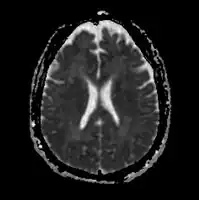

Acute severe hepatic encephalopathy -

Acute severe hepatic encephalopathy

The diagnosis of hepatic encephalopathy is a clinical one, once other causes for confusion or coma have been excluded; no test fully diagnoses or excludes it. Serum ammonia levels are elevated in 90% of people, but not all hyperammonaemia (high ammonia levels in the blood) is associated with encephalopathy.[3][8] A CT scan of the brain usually shows no abnormality except in stage IV encephalopathy, when brain swelling (cerebral oedema) may be visible.[8] Other neuroimaging modalities, such as magnetic resonance imaging (MRI), are not currently regarded as useful, although they may show abnormalities.[14] Electroencephalography shows no clear abnormalities in stage 0, even if minimal HE is present; in stages I, II and III there are triphasic waves over the frontal lobes that oscillate at 5 Hz, and in stage IV there is slow delta wave activity.[3] However, the changes in EEG are not typical enough to be useful in distinguishing hepatic encephalopathy from other conditions.[14]